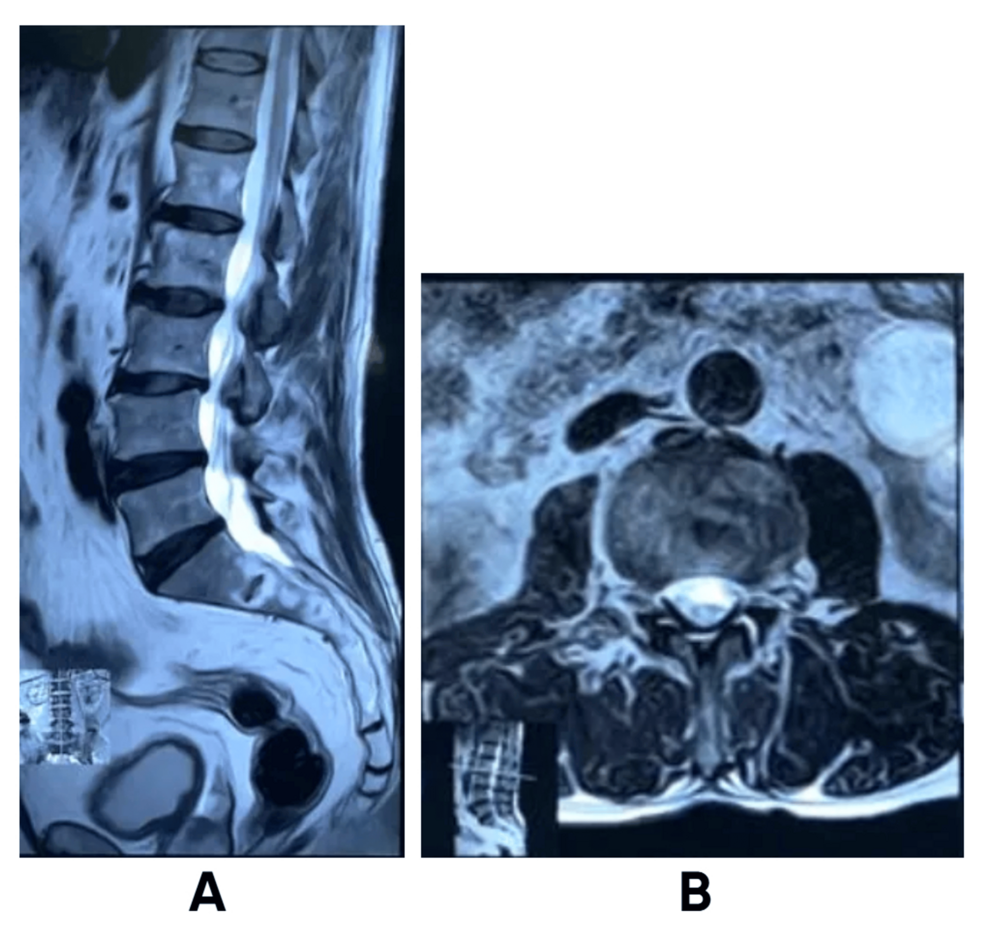

* Imaging Concerns: Despite initial normal radiographs,persistent clinical suspicion led to the ordering of an MRI of the lumbar spine and brain.

The brain MRI revealed a large, extra-axial mass located in the parasagittal region, consistent with a meningioma. Crucially, the tumor was compressing the underlying brain tissue and disrupting corticospinal tracts responsible for lower limb motor function. This compression was the root cause of the patient’s symptoms, effectively mimicking peroneal neuropathy.

Diagnostic Confirmation & Surgical Intervention

Following the MRI findings, a surgical consultation was obtained. A craniotomy was performed, and the meningioma was completely resected. histopathological examination confirmed the diagnosis of a World Health Institution (WHO) Grade I meningioma.

Post-operatively, the patient experienced a gradual but significant improvement in his right foot strength and gait.The foot drop resolved over several months with continued physiotherapy. Follow-up neurological examinations demonstrated a return to near-normal function. This case underscores the importance of considering intracranial pathology in patients presenting with atypical neurological symptoms.